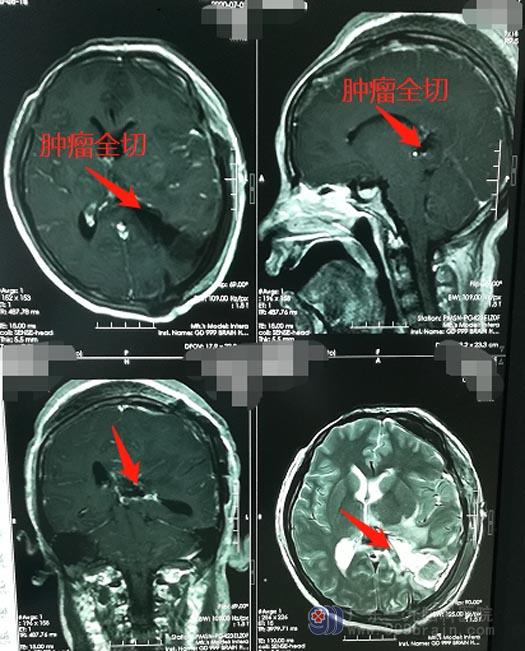

神经外五科医生团队一致认为,手术切除肿瘤是目前最佳的治疗方式,家属也非常认可并积极配合。6月29日,医院副院长、神经外五科主任鲁明带领手术团队给小美实施了“左侧侧脑室巨大占位切除术”,显微镜下将肿瘤全部切除,手术很顺利;术后病理结果提示,肿瘤为良性的脑膜瘤。